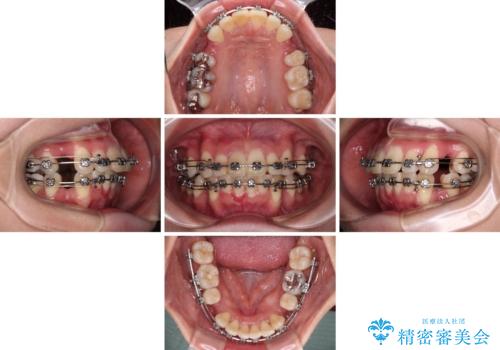

- 矯正装置

- メタルブラケット

- 八重歯と上の前歯が出っ歯になっていることを気にして来院された患者様です。

横から見た際の口元の飛び出した印象も改善したいとのことで、上下左右の第一小臼歯4本を抜歯し、ワイヤー装置にて抜歯矯正を行うこととしました。

前歯の変色している歯は、神経組織が壊死していたため、矯正治療前に根管治療を実施し、矯正治療後にオールセラミッククラウンにて補綴治療を行うこととしました。